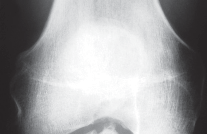

Developmental Dislocation (Dysplasia) of the Hip (DDH)-IMAGING AND OTHER DIAGNOSTIC STUDIES ■ Dynamic hip ult…